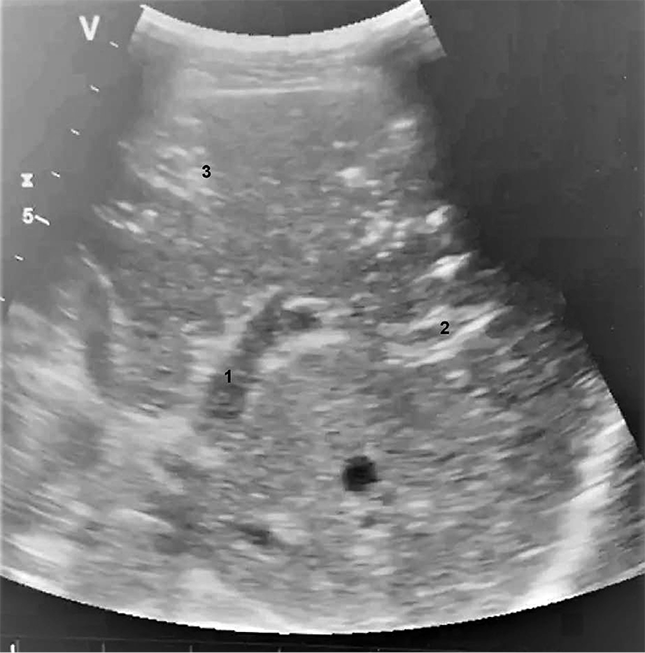

Представлен клинический случай раннего хирургического лечения абдоминального компартмент-синдрома, возникшего после аортобедренного бифуркационного шунтирования. Мужчина 73 лет поступил в СЗГМУ им. И.И. Мечникова с критической ишемией нижних конечностей. В плановом порядке выполнили аортобедренное бифуркационное шунтирование синтетическим протезом через лапаротомный доступ. Послеоперационный период осложнился динамической кишечной непроходимостью. Прогрессировало ухудшение состояния (гиповолемический и септический шок, дыхательная недостаточность на фоне тяжелой пневмонии). Изначальная хирургическая тактика состояла в консервативном ведении. После выявления с помощью прикроватного ультразвукового исследования признаков интестинальной ишемии (пневматоз стенки кишечника, газ в воротной вене) тактику изменили. В тот же день провели декомпрессионную релапаротомию, установили интестинальный зонд. Послеоперационный период протекал с положительной динамикой: ранняя экстубация с удовлетворительными показателями газообмена, минимальные дозировки вазопрессорной поддержки, появление стула на 2-й день после операции.

Газ в воротной вене в 70 % случаев свидетельствует о некрозе стенки кишечника. Выявление этого ультразвукового феномена у пациентов после операций на брюшном отделе аорты может указывать на ишемию толстой кишки, поскольку нарушения мезентериального кровообращения в первую очередь развиваются в бассейне нижней брыжеечной артерии. Состояние требует экстренного хирургического вмешательства, но его дифференциальная диагностика с послеоперационным парезом кишечника не всегда возможна, особенно на ранних стадиях. В нашем случае раннее выявление газа в воротной вене и экстренное вмешательство по этому поводу предотвратили необратимое ишемическое повреждение кишечника. Прикроватный ультразвуковой мониторинг позволяет предположить данное состояние и определить показания к раннему хирургическому вмешательству, что может улучшить исход.